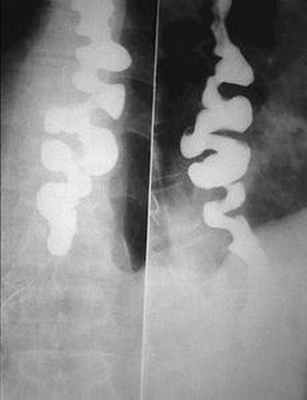

Особое место среди функциональных нарушений занимает так называемая ахалазия, включающая в себя такие прежние понятия, как «кардиоспазм» и «идиопатическое расширение пищевода». Она обусловлена стойким нарушением функции (раскрытия) пищеводно-желудочного перехода, сопровождающимся равномерным расширением и удлинением пищевода, отсутствием нормальной перистальтики, коническим (в виде «крысиного хвоста») сужением диафрагмального и абдоминального сегментов пищевода, задержкой опорожнения и резким уменьшением размеров или полным отсутствием газового пузыря желудка. Степень выраженности этих изменений и обусловленная ими рентгенологическая картина зависят от стадии ахалазии. Так, в начальной стадии грудной отдел пищевода расширен незначительно, имеет цилиндрическую форму, перистальтирует.

Однако первичная перистальтическая волна, появляющаяся при проглатывании большой порции бариевой взвеси, достигает лишь средней трети пищевода и там исчезает. Узкий терминальный сегмент пищевода открывается с трудом лишь после заполнения пищевода и быстро закрывается еще до того, как наступит полное его опорожнение. Газовый пузырь желудка заметно не изменен. Клинические проявления минимальны или отсутствуют.

Во второй (субкомпенсированной) стадии ахалазии расширение грудного отдела пищевода выражено больше, тонус его понижен. Желудочно-пищеводный переход открывается кратковременно лишь после тугого заполнения всего пищевода. В этой стадии ахалазию необходимо дифференцировать от стенозирующей формы рака пищевода и стенозирующего эзофагита. В пользу эзофагита свидетельствуют соответствующие изменения рельефа слизистой оболочки, наличие перистальтики, прослеживаемой до диафрагмального сегмента пищевода, а также отсутствие газового пузыря желудка.

В третьей стадии ахалазии (стадии декомпенсации) пищевод резко расширен, удлинен и изогнут, вследствие чего он значительно выступает вправо, обусловливая расширение срединной тени («идиопатическое» расширение). Содержит остатки пищи и газ. Стенки пищевода атоничные, вялые, не перистальтируют. Абдоминальный сегмент стойко сужен, раскрывается редко, кратковременно и не полностью. Полного опорожнения пищевода не наступает. Газ в желудке отсутствует.

Рельеф слизистой оболочки в суженной части пищевода сохранен, в остальных же его отделах отчетливо видны проявления диффузного эзофагита (грубый, пятнистый или «шагреневый» рельеф).